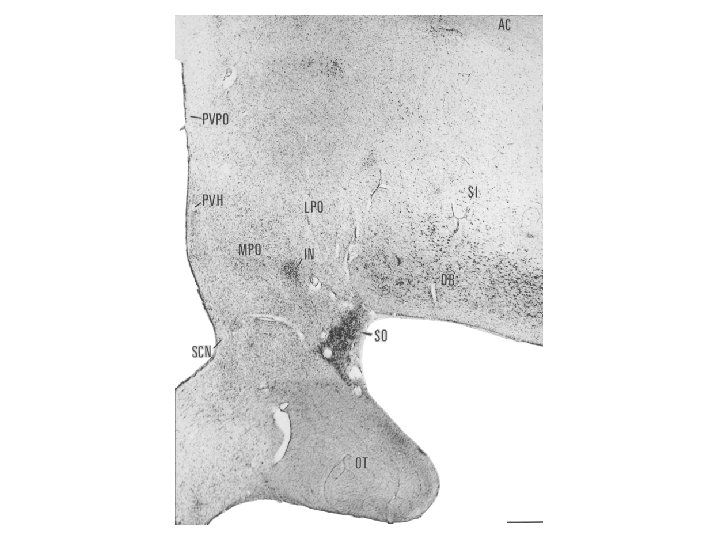

Hypothalamus szerepe a só- és vízháztartás szabályozásában A vasopressin a magnocellularis paraventricularis és supraopticus magokban termelődik. A vasopressint korábban antidiureticus hormonként (ADH) írták le, és ez az elnevezés ma is használatos a klinikumban. A vasopressin szintézisében és a neurohypophysisbe juttatásában, illetve az onnan történő felszabadításában két másik hormon az angiotensin II, és atrialis natriureticus hormon visz szerepet. Az előző a vesében termelődő renin-angiotensin rendszer aktív tagja, mely a vér-agy-gát-mentes subfornicalis szerven keresztül jut be az agyba, míg az utóbbit a preopticus area neuronjai termelik.

Nucleus paraventricularis hypothalami A hypothalamus egyik legjelentősebb magja, magno- és parvocellularis részre osztható. A magnocelluláris neuroszekretoros sejtek vasopressint és oxytocint termelnek, axonjaik a tractus hypothalamo-hypophysealis egy részét alkotják, és a hypothalamus hátulsó lebenyében végződnek. A parvocelluláris neuroszekretoros idegsejtek több peptiderg neurohormont (corticotropin-releasing hormon – CRH, thyrotropin-releasing hormon – TRH, vasopressin) és neuromodulátort (neuropeptidet) termelnek. A parvocellularis neuronok egy része az eminentia mediana portális erei révén juttatja el termékét a hypophysis elülső lebenyébe, másik részük a nyúltvelőbe és a gerincvelőbe projíciál. A CRH-termelő idegsejtek révén a paraventriculáris magot a stresszválasz központi részének, a „hypothalamohypophysis-mellékvesekéreg szabályozó rendszer” („HPA axis”) kiinduló pontjának tekintik.